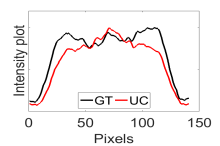

The calculated correlation coefficient (), SNR, as well as CNR values for all tested methods in the synthetic phantom experiment are shown in Table II. As seen in Table II, the proposed NCBC method achieved the highest , CNR as well as SNR values when compared to that of other tested methods. Visual results from the bias-corrected DW-MR synthetic phantom data produced using different tested methods is shown in Fig. 2(c-i). It can be observed that the MCBC, LEMS, and proposed NCBC method were able to achieve the best level of bias correction when compared to the other tested methods. This is particularly apparent in the peripheral zone (PZ) of the prostate gland as highlighted using red ROIs in Fig. 2(a-i), where intensity inhomogeneities are still present to a significant degree in the bias-corrected phantom data produced using the LS, SCIC, SGD and BCFCM methods, while strong inhomogeneity correction performance is achieved using MCBC, LEMS, and the proposed NCBC method. Furthermore, it can be observed that NCBC exhibited minimal intensity inhomogeneities when compared with MCBC and LEMS, particularly in the area that is highlighted using Red ROIs. To better represent the outperforming of proposed NCBC method in terms of bias correction using synthetic phantom, the data intensity profiles corresponding to the drawn blue line in Fig. 3(a) are shown in Fig. 3(b) for uncorrected data (red color plot) versus ground truth data (black color plot) and in Fig. 3(c-i) for corrected data using different tested methods (red color plots) versus ground truth data (black color plots). As the intensity profiles of Fig. 3(b-i) show, NCBC method was resulted in an intensity profile with the most flatness and less amount of variation compared to the intensity profiles of uncorrected image as well as reconstructed images using other tested methods as such confirms the better performance of proposed NCBC method in terms of bias field correction.